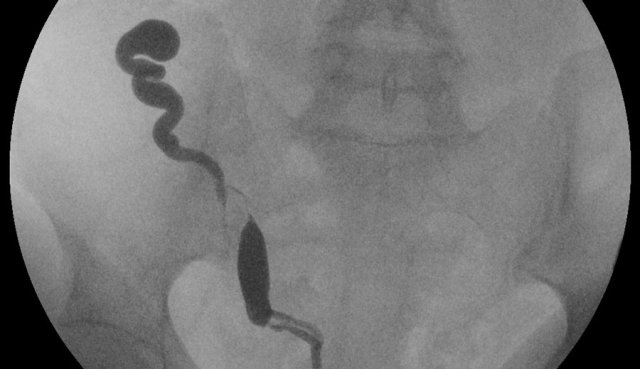

In this patient the HSG shows a single, off-midline cavity with a hydrosalpinx.

Further analysis was done with MRI.

Continue with the MR-images.

The subsequent MRI shows a small, curved and off-midline positioned uterus on the right.

No rudimentary horn is present on the left side.

The cervix is not necessary to mention in the final classification of this case, since a hemi-uterus it is usually accompanied by unilateral cervical aplasia.

The vagina does not show any abnormalities (V0).

Kidneys showed normal anatomy (not shown).

Classification: U4bV0.